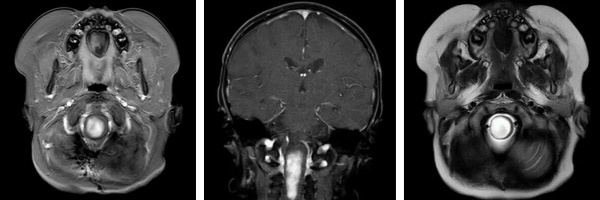

術(shù)前影像(MRI)

懷著最后一線希望,阿什利一家跨海越洋,來到我院腦腫瘤科求助。入院時,患兒右側(cè)肢體活動嚴重受限,面癱癥狀逐漸顯現(xiàn)。影像檢查顯示腫瘤位于腦干中央,與周圍重要神經(jīng)結(jié)構(gòu)和血管關(guān)系密切,手術(shù)難度極大、風險極高。